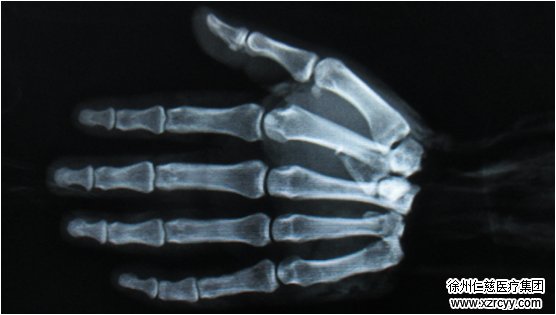

郑主任介绍:“患者被送来的时候,右腕自掌腕关节处完全断离,创面创缘不齐,挫伤、污染严重。”高倍显微镜下,郑大伟、吴尧、杨雯三位医护人员联手,将骨折的右侧尺骨复位内固定、将第1掌关节脱位复位内固定,并逐一修复缝合被损伤的神经、血管、肌腱、肌肉、韧带。

整台手术持续8个多小时,在医护人员出色的配合下,高难度的断掌再植手术顺利完成。